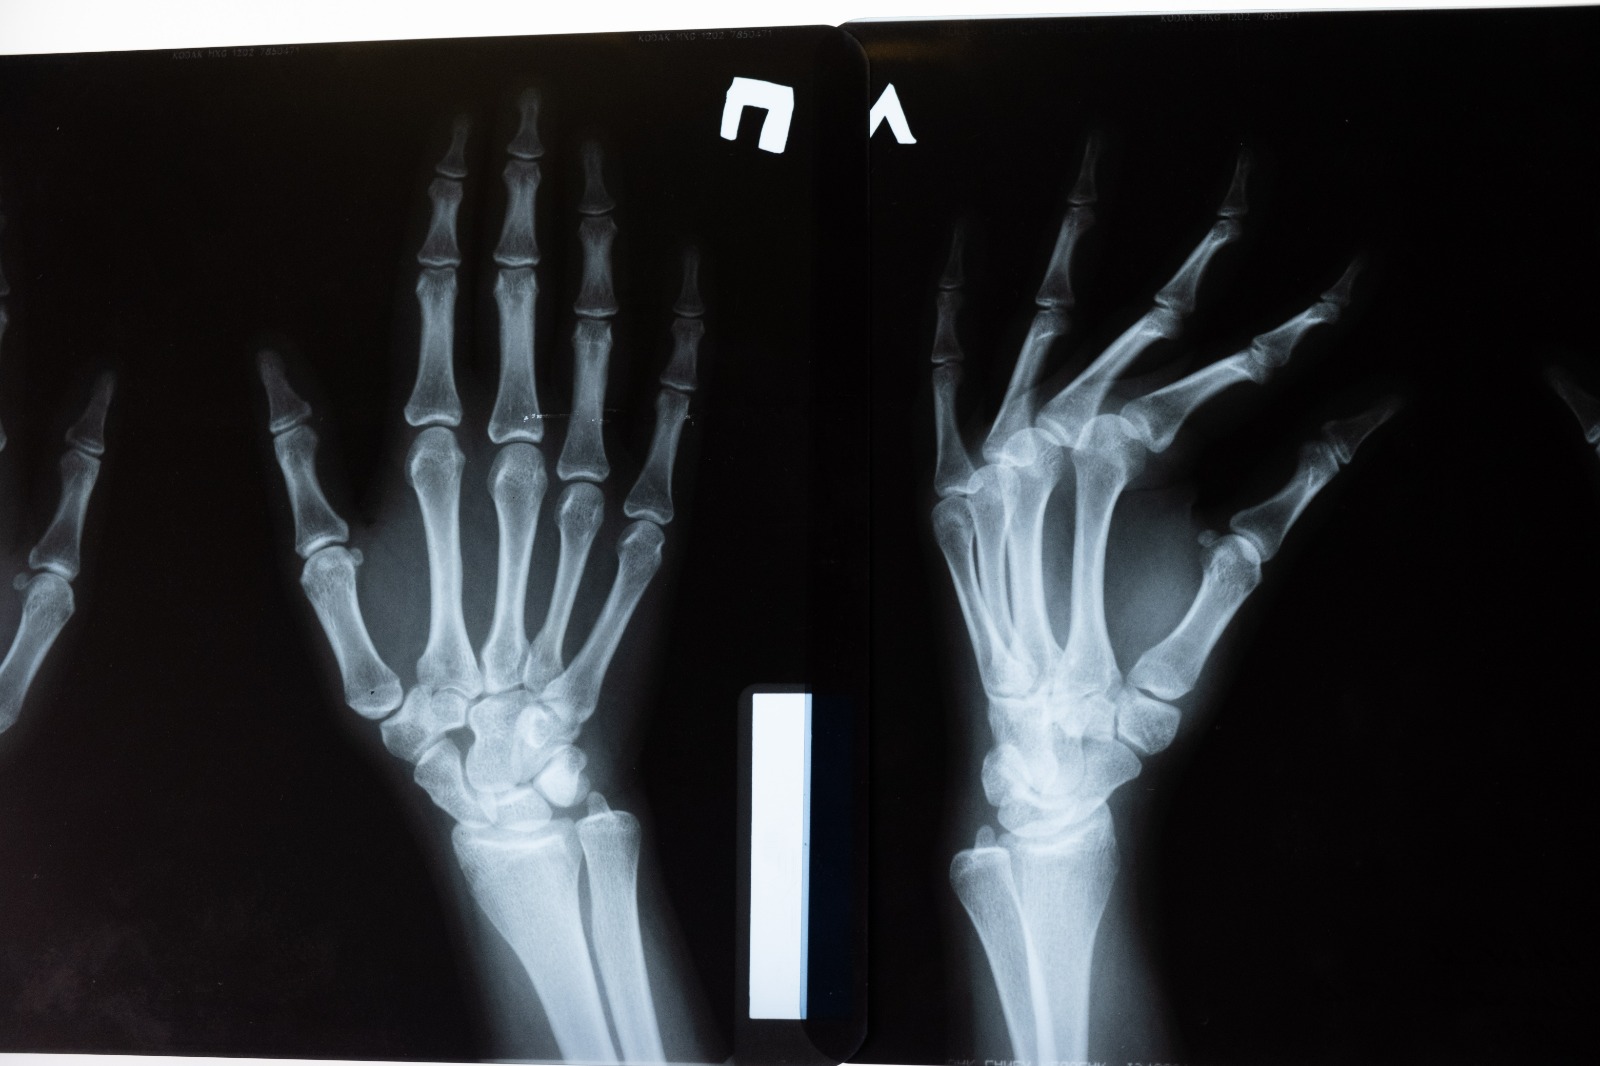

Çekiç Parmak

Çeşitli sebeplerden kaynaklı el ve ayaklarda meydana gelen şekil bozuklarına verilen addır. Genellikle el ve ayağı ikinci parmaklarında görülür.

Ayak başparmağını etkileyen bunyonun tersine, çekiç parmak herhangi bir ayak parmağında oluşabilir (en sık ikinci parmak). Ayak parmağı kıvrılır ve ağrır. Genel olarak ayak parmağındaki her iki eklem de etkilenerek, parmak pençeye benzer bir görünüm alır. Çekiç parmak, küçük ayakkabı giymenin sonucu oluşabilir, ancak kas ve sinir hasarı oluşmuş şeker hastalarında da meydana gelir.